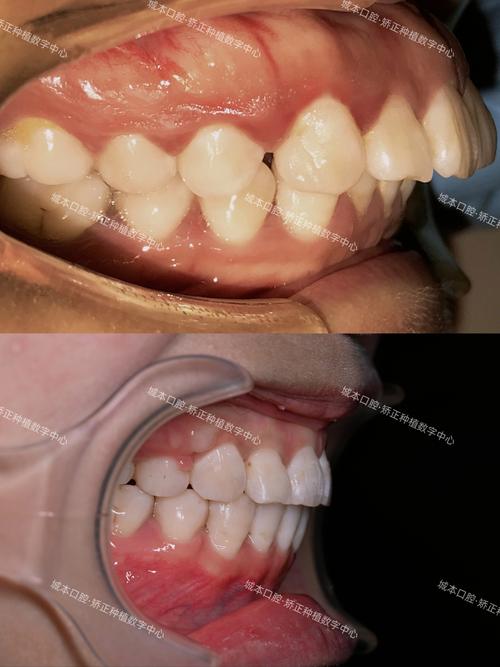

部分患者(尤其是成年人或存在牙周病史者)在治疗前即存在牙槽骨吸收(如牙周炎导致的牙槽骨height降低、宽度变窄),或治疗过程中因口腔不良习惯(如吐舌、咬唇)、矫治力不当等因素引发牙槽骨继发性吸收,牙槽骨支持不足会降低牙齿抵抗侧向力的能力:当去除矫治器后,牙齿在咬合力、肌肉功能(如唇肌、舌肌)的作用下发生倾斜、移位,表现为牙冠唇倾/舌倾、牙间隙重新出现等,上颌前牙唇倾患者常伴有牙槽骨唇侧骨板较薄,若治疗中未通过骨增量技术改善骨量,治疗后前牙在唇肌压力下极易复发唇倾。